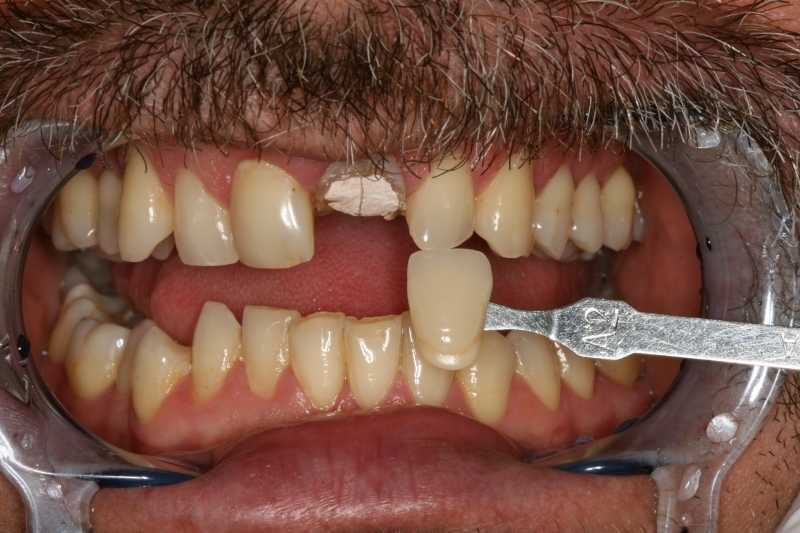

45 éves férfipáciensünk a képen látható státusszal érkezett klinikánkra: letört és nem korrekt gyökértöméssel rendelkező bal felső nagymetszővel, ill. régi, elszíneződött töméssel bíró, formáját tekintve kedvezőtlen esztétikájú jobb felső nagymetsző foggal.

A megfelelő esztétikai végeredmény érdekében fogtechnikai laborunk nagyfelbontású fotók alapján dolgozott.

fogtechnikai laborunk nagy felbontású fotók alapján dolgozik